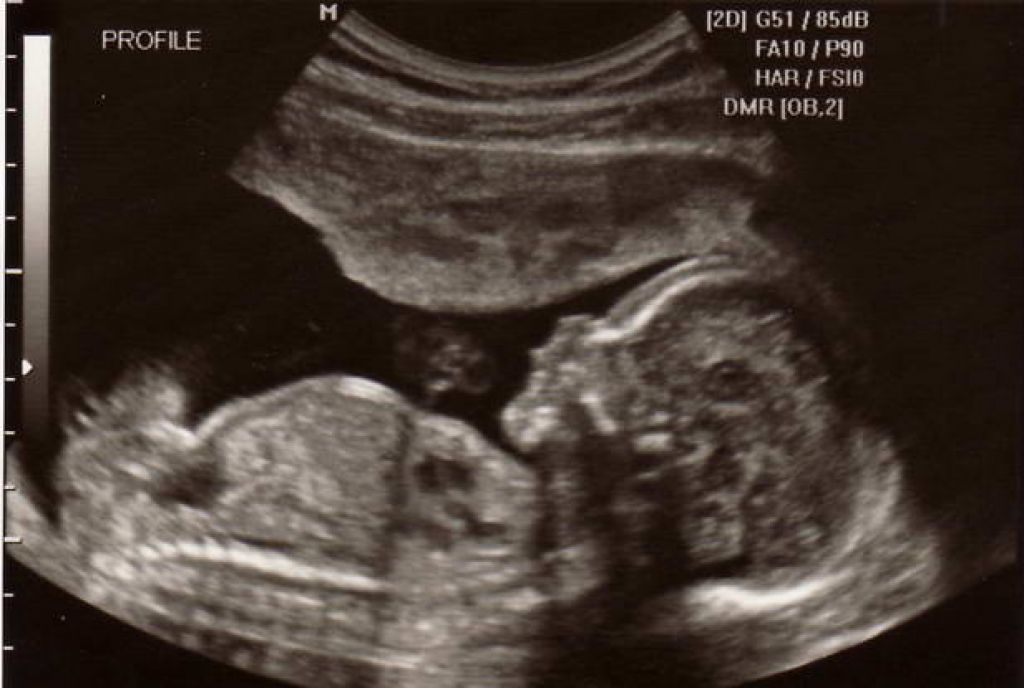

Как проходит УЗИ определение пола ребенка в медцентре МЕД ПРОЕКТ?

Сделать качественное и недорогое УЗИ определение пола ребёнка в Москве можно в любое для пациентки время в стенах стационара современного медицинского центра «Мед Проект» с помощью индивидуального подхода к предоставлению диагностической помощи. Данная методика обследования — одна из самых востребованных для беременных девушек, которая помогает безопасно определить гендерную предрасположенность будущего малыша.

Данный метод неинвазивной диагностики позволяет достоверного и детально осуществить визуализацию наружных половых органов плода, которое и позволит определить гендерную предрасположенность.

При обнаружении пениса и мошонки можно точно сделать вывод о том, что внутриутробно развивается мальчик. При обнаружении половых губ врачам удаётся распознать девочку. В особенно редких случаях специалист может определить гермафродитизм, на фоне которого плод имеет хромосомный набор одного пола, а половые органы — другого. И в таком случае дополнительно может потребоваться осуществление инвазивного или неинвазивного генетического выявления пола плода. И данная услуга также может быть осуществлена в нашем центре медицины «Мед Проект» в Москве. Вы можете сделать у нас УЗИ органов грудной клетки, или любого другого органа.

Данная методика может проводиться на сроке с 16 недели, когда происходит завершение первого важного этапа развития и созревания половых органов у малыша. Это позволит снизить до минимума вероятность ошибок, которые допускаются на более ранних сроках. Показатель точности и достоверности получаемого результата на таком благоприятном сроке составляет более 95%.

В результате прохождение такого ультразвукового исследования пациентка получает официальный протокол обследования, где указывается точный срок беременности и пол малыша. Вместе с ним девушка получает снимки, где можно рассмотреть пенис или половые губы, свидетельствующие об ожидании на свет мальчика или девочки.

Даная методика имеет точность результатов до 95%. В некоторых случаях при её выполнении не удаётся определить гендерного типа плода, поскольку при его положении в животе не проводится визуализация половых органов. Например, они могут быть закрыты пуповиной или их накрывает плацента.